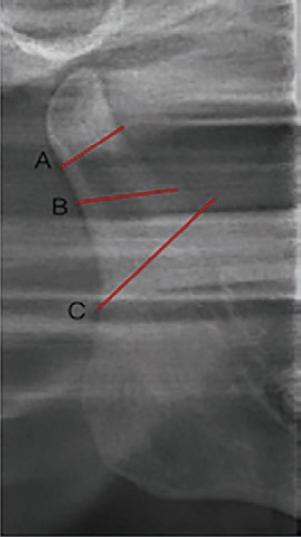

Within the study in relation to condylar fractures there are classifications for the denomination to the location of the same ones. According to Loukota, fractures are classified in diacapitular, neck, and base. Diacapitular fractures being those fractures compromising the head of the condyle, in which the line begins at the articular surface, being able to extend outside the capsule. Neck fractures of the condyle include fractures that begin above the sigmoid recess. And finally, the base fractures (subcondylar) are those whose fracture line is below the sigmoid recess3-5 (Fig. 1).

Figure 1 Location of condylar fractures: A: Neck fractures; B: Subcondylar fractures; C: Diacapitular fractures.

Likewise, MacLennan and Lindahl establish a classification with greater acceptance, defining fractures as condylar head, neck, and subcondylar fractures with the same parameters previously mentioned, as well as dislocation and displacement6 (Fig. 2).